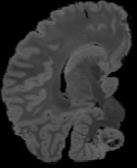

In neuroimaging, MRI tissue properties characterize underlying neurobiology, provide quantitative biomarkers for neurological disease detection and analysis, and can be used to synthesize arbitrary MRI contrasts. Estimating tissue properties from a single scan session using a protocol available on all clinical scanners promises to reduce scan time and cost, enable quantitative analysis in routine clinical scans and provide scan-independent biomarkers of disease. However, existing tissue properties estimation methods - most often $\mathbf{T_1}$ relaxation, $\mathbf{T_2^*}$ relaxation, and proton density ($\mathbf{PD}$) - require data from multiple scan sessions and cannot estimate all properties from a single clinically available MRI protocol such as the multiecho MRI scan. In addition, the widespread use of non-standard acquisition parameters across clinical imaging sites require estimation methods that can generalize across varying scanner parameters. However, existing learning methods are acquisition protocol specific and cannot estimate from heterogenous clinical data from different imaging sites. In this work we propose an unsupervised deep-learning strategy that employs MRI physics to estimate all three tissue properties from a single multiecho MRI scan session, and generalizes across varying acquisition parameters. The proposed strategy optimizes accurate synthesis of new MRI contrasts from estimated latent tissue properties, enabling unsupervised training, we also employ random acquisition parameters during training to achieve acquisition generalization. We provide the first demonstration of estimating all tissue properties from a single multiecho scan session. We demonstrate improved accuracy and generalizability for tissue property estimation and MRI synthesis.